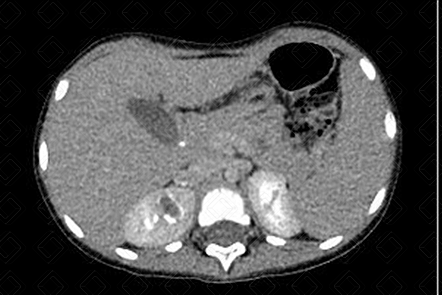

Texto alternativo para a imagem Figura 1. Créditos: Dra. Elazir Mota - Rio de Janeiro/RJ

Descrição das figuras 1 e 2: Tomografia computadorizada do abdome nas fases portal (esquerda) e excretora (direita) evidenciando falha de enchimento na topografia do cálice menor e pirâmide, com preenchimento periférico do contraste (seta vermelha), por necrose papilar.

• Urotomografia: A pesar da radiação ionizante, tem sido um exame cada vez mais utilizado para confirmar este diagnóstico. Observaremos um cálice convexo com extravasamento de contraste para a papila renal, na maioria dos casos (f iguras 1 e 2) . No caso apresentado, tratava-se de paciente com tuberculose - observe os linfonodos calcificados no mesentério (f igura 3) .